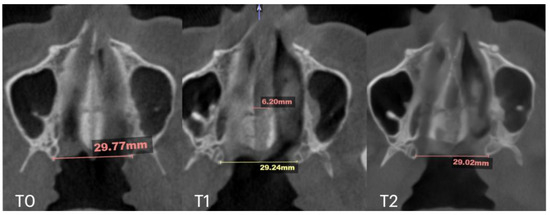

2.7. Case D: Midfacial Asymmetry Correction with Guided Expansion

| Nasal Base Width, mm | Maxillary Base Width, mm | Lateral Nasal Width, mm | Inter-Pterygoid Distance, mm | Midpalatal Suture Separation, mm | |||||||||

|---|---|---|---|---|---|---|---|---|---|---|---|---|---|

| T0 | T1 | T2 | T0 | T1 | T2 | T0 | T1 | T2 | T0 | T1 | T2 | T1 | |

| Case A | 30.84 | 38.15 | 38.37 | 59.22 | 66.37 | 67.11 | 32.8 | 39.33 | 39.48 | 28.01 | 32.88 | 33.38 | 10.5 |

| Case B | 30.61 | 34.41 | 34.97 | 59.73 | 63.47 | 60.56 | 31.79 | 34.6 | 35.35 | 29.18 | 31.38 | 34.59 | 5.7 |

| Case C | 28.40 | 38.32 | 36.72 | 53.63 | 62.43 | 59.80 | 31.29 | 38.45 | 38.51 | 29.15 | 35.8 | 35.36 | 8.47 |

| Case D | 26.25 | 33.27 | 31.54 | 55.9 | 61.84 | 60.37 | 33.98 | 35.94 | 38.09 | 29.77 | 29.24 | 29.02 | 6.2 |